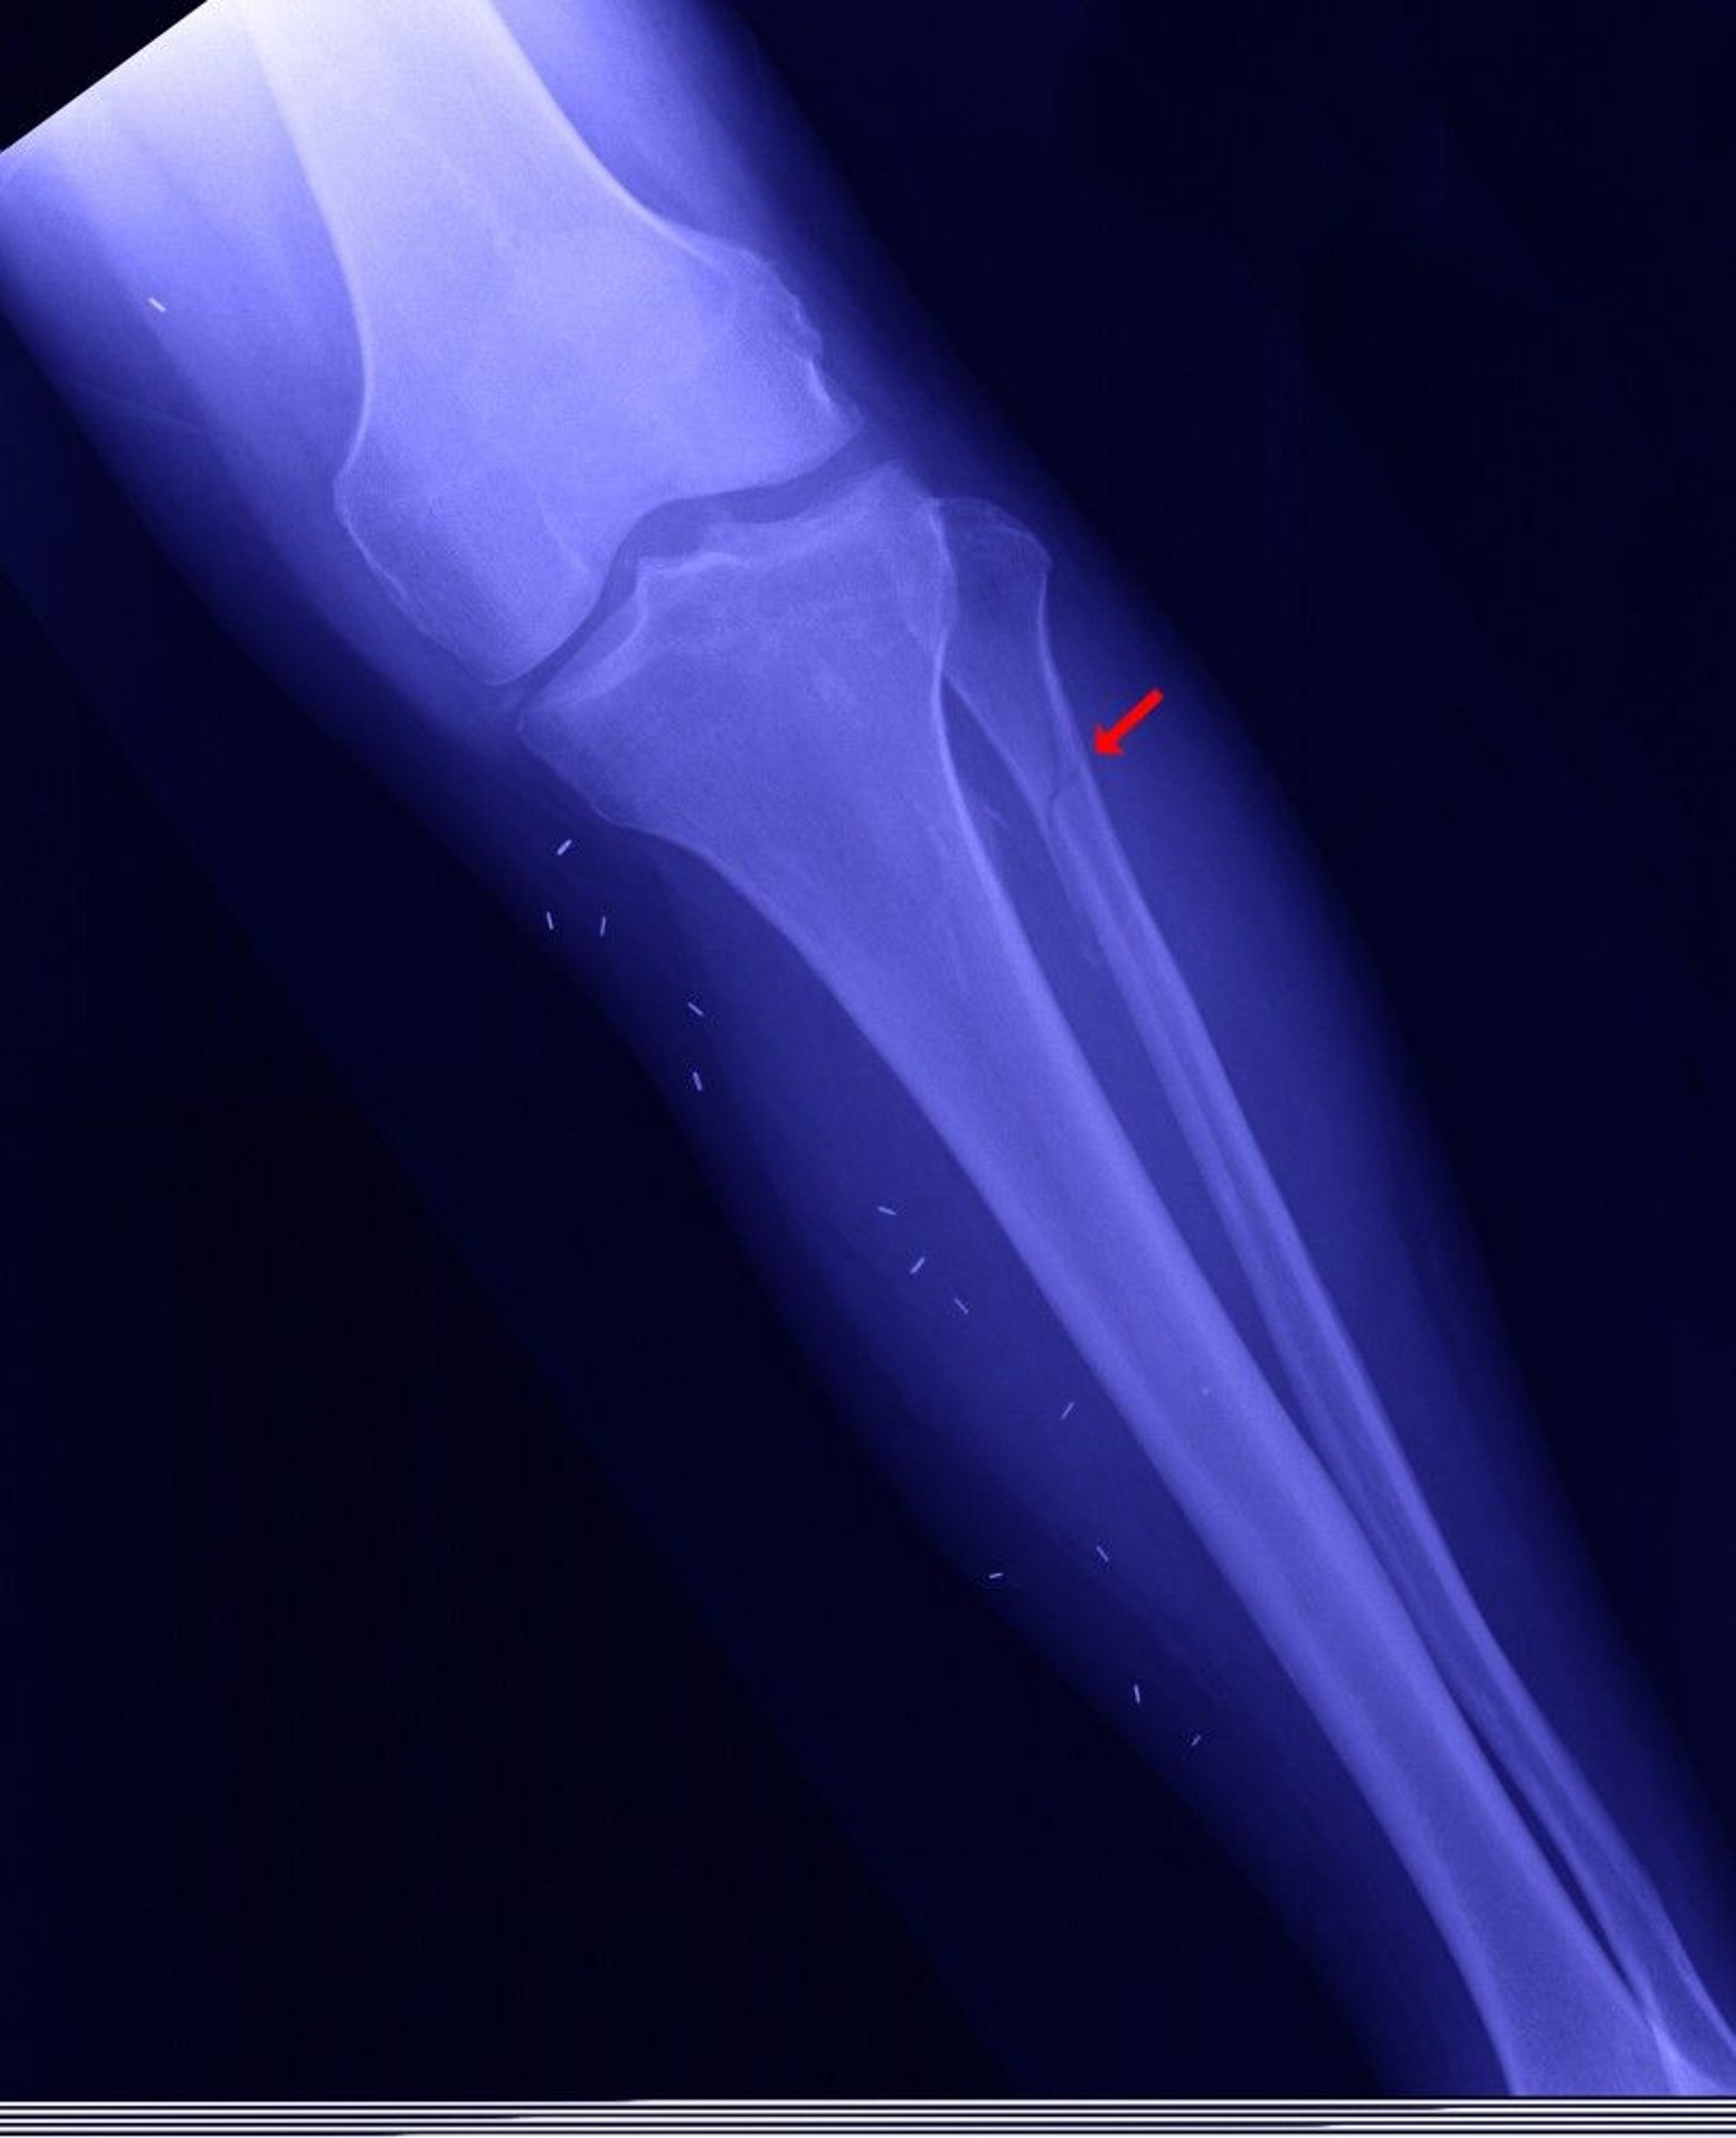

Proximal Fibular Fracture

The proximal fibula may be fractured (called a Maisonneuve fracture—shown here), when the medial malleolus is fractured, the ankle mortise (the joint between the tibia and the talus) is open, and the distal fibula is not fractured.

EDWARD KINSMAN/SCIENCE PHOTO LIBRARY